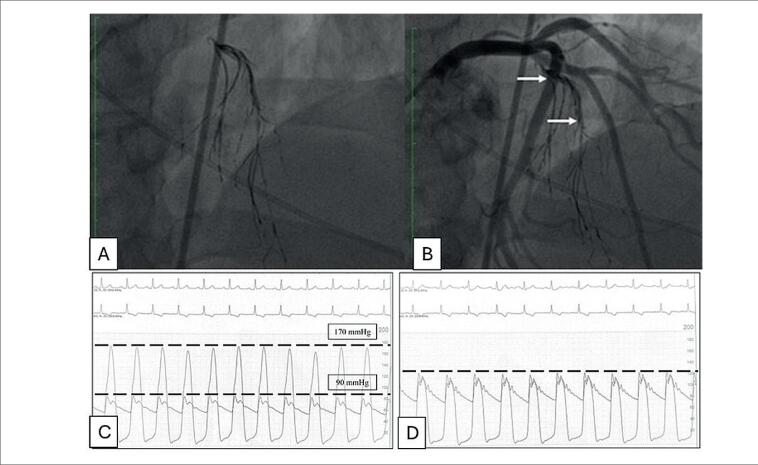

Septal Artery Embolization with Onyx® In Hypertrophic Cardiomyopathy: Report of Two Cases.